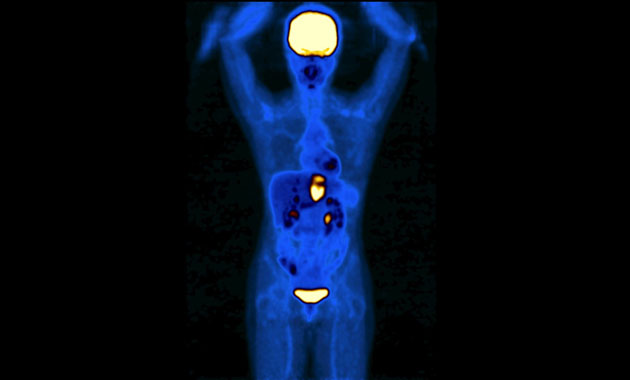

The Molecular Imaging and Therapeutics (MI&T) division, at UCSF Department of Radiology & Biomedical Imaging, oversees the clinical practice of traditional nuclear medicine, including multimodality PET/CT and PET/MR, and stewards the application of molecular therapeutic agents for our patients. The division will also work closely with the Chemistry, Probes and Molecular Therapy (CPMT) Specialized Resources Group within the department, as well as with clinicians and researchers in other departments such as oncology, cardiology and neuroscience, to usher in a new generation of imaging and treatment modalities.

- Advanced diagnostic molecular imaging modalities including new PET/CT and PET/MRI methods

- Experience in comprehensive multi-modality imaging of cancer and advanced nuclear cardiology imaging studies